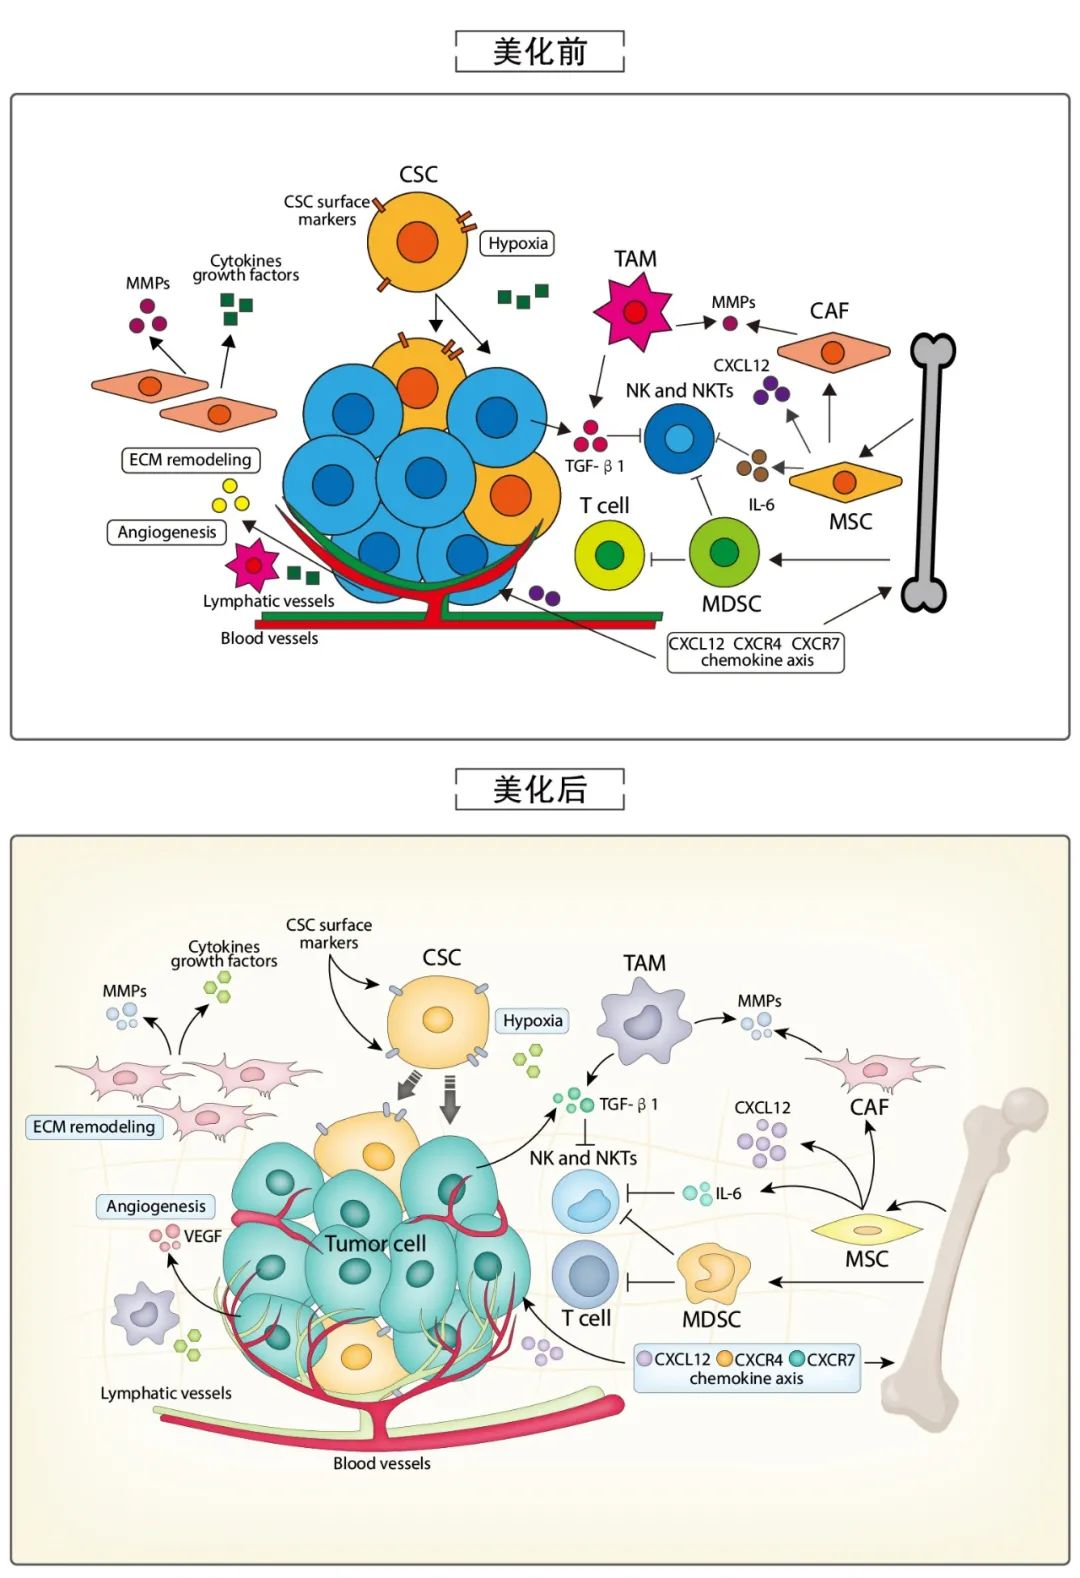

论文图表美化

滑动查看更多 点击查看大图